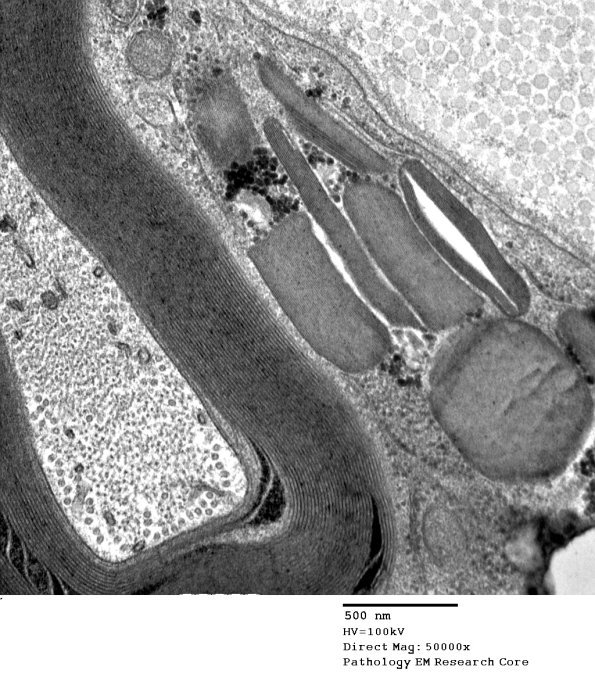

3A2,3 Higher magnification images of Pi granules in this case. (Electron micrographs)